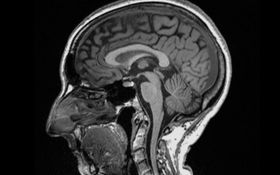

According to a recent study, the phenomena referred to as covid brain may not only be real but new data also suggests that it may cause people’s brain to shrink.

As per the research carried out on 785 UK Biobank participants and published in the peer-reviewed multidisciplinary science journal, Nature, three key long-term effects were observed:

“(i) greater reduction in grey matter thickness and tissue-contrast in the orbitofrontal cortex and parahippocampal gyrus, (ii) greater changes in markers of tissue damage in regions functionally-connected to the primary olfactory cortex, and (iii) greater reduction in global brain size.”

Observing subjects aged between 51 and 81 who underwent two brain scans – 401 of which suffered a coronavirus infection between their first and second scan – on average, infected showed “cognitive decline between the two timepoints”.

It was found that even after mild infections, the overall size of the participants’ brain had shrunk slightly, with less grey matter in the regions related to smell and memory, specifically – hence people reporting side effects such as ‘brain fog‘ and prolonged symptoms like loss of their olfactory senses.